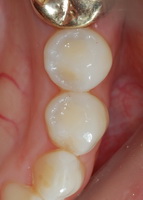

| ±ÝÀη¹ÀÌ¿Í Å©¶ó¿î |